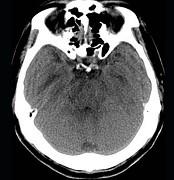

问题 男,57岁,头痛、头晕1周,言语不清,饮水呛咳两天,既往有鼻咽癌病史,给予放射治疗,CT检查如图所示,最可能的诊断为()

选项 A.脱髓鞘病变 B.脑炎 C.放射性脑病 D.脑梗死 E.胶质瘤

答案 C